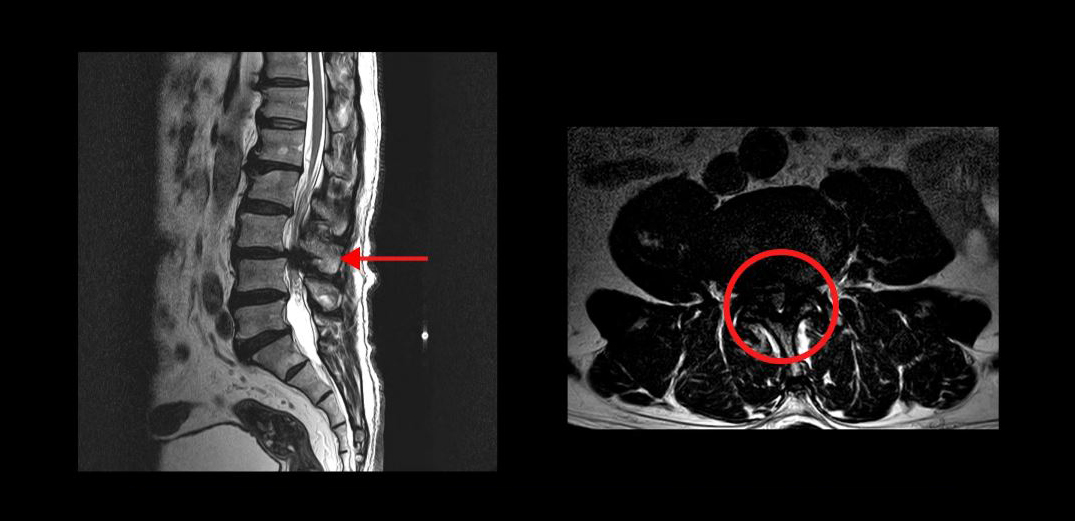

다음은 두 번째 케이스의 환자분입니다.

이 분은 MRI를 보시면 척추관 한 마디가 심하게 막혀있는 중심성 척추관협착증 환자분입니다. 이분은 10년 이상 협착증 증상을 앓다가, 결국 조금만 걷기만 하면 다리에 힘이 빠져버려서 아무데라도 주저 앉아야 하는 극심한 신경성 파행 증상을 겪으셨습니다. 서울의 유명 대학병원에서 수술을 하기로 했지만, 심장 문제 때문에 결국 수술을 못 받으신 환자분입니다.